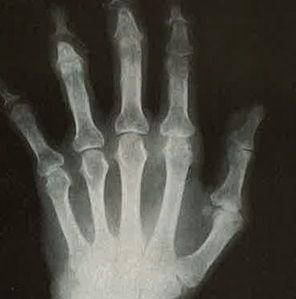

A 56-year-old woman presents to your office with persistent pain and tenderness in both hands on palpation. Her body mass index (BMI) is 37 kg/m2, and her blood pressure is 135/85 mm Hg. A workup reveals that the patient has erosive osteoarthritis of the hand.

Which factors are most strongly associated with increased pain in erosive OA of the hand?